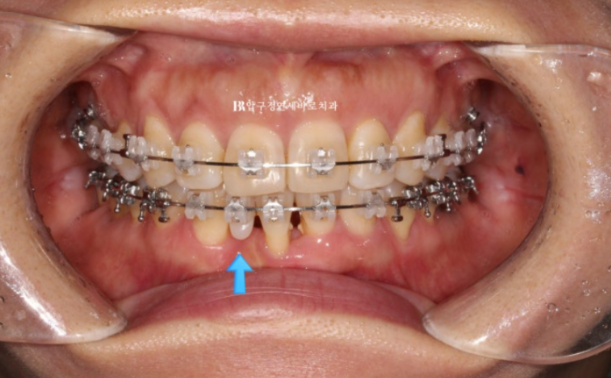

파란 화살표 부위가 치주염이 심한 부위입니다.

앞니 4개 중 3개가 모두 흔들리며 치주염이 깊은 상태여서 발치가 불가피한 상황입니다.

3개 중 2개는 발치를 하고 나머지 1개는 많이 흔들리지만 쓸때까지 쓰다가 나중에 빠지면 보철을 하기로 정하고 교정치료를 했습니다.

23.03

가장 상태가 안 좋은 아래 앞니 1개를 먼저 발치하고 클리피씨 장치로 나머지 치아를 배열합니다.

순차적으로 발치하는 이유는 처음부터 2개를 한 번에 빼면 빈공간이 너무 크기 때문입니다.